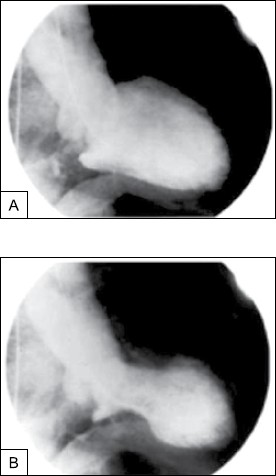

Mulher de 62 anos, previamente saudável, apresenta dor torácica subesternal e dispneia nas últimas 2 horas. O desconforto começou minutos depois de saber que seu filho havia se ferido gravemente em um acidente automobilístico. O histórico é notável para hipertensão arterial. Exame físico: pressão arterial: 152 x 84 mmHg; frequência cardíaca: 88 bpm; saturação de O2: 96%; tórax normal; exame cardíaco: não há galope ou sopro; extremidades sem edema. ECG: inversões difusas da onda T. Exames laboratoriais são inespecíficos e a troponina cardíaca é de 1,07 ng/mL (normal <0,01 ng/mL). O desconforto torácico persiste, apesar da nitroglicerina IV, e a angiografia coronária é realizada. Não são encontradas estenoses coronárias. A ventriculografia esquerda é mostrada a seguir.

(Arquivo pessoal: imagem usada com autorização.)